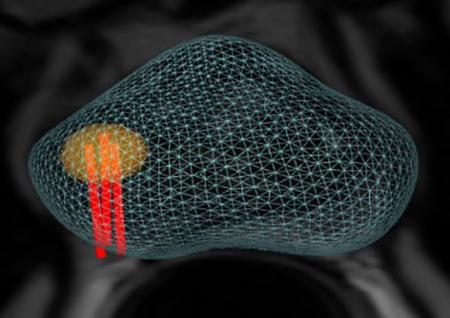

Με την νέα μέθοδο επιτυγχάνεται με απόλυτη ακρίβεια η λήψη υλικού βιοψίας αποκλειστικά και μόνο, από τα προς διερεύνηση εντοπισμένα ύποπτα σημεία, που έχουν ήδη αναδειχθεί στην προηγηθείσα πολυπαραμετρική μαγνητική τομογραφία προστάτη.

- Την ελαστική συγχώνευση τρισδιάστατων εικόνων Υπερηχογραφήματος και Μαγνητικής Τομογραφίας σε πραγματικό χρόνο μέσω του λειτουργικού συστήματος εντοπισμού Organ-Based Tracking Fusion( OBT Fusion).

- Aπεικόνιση του προστάτη σε τρισδιάστατη μορφή.

Ακολουθούν Εικόνες

OBT FUSION